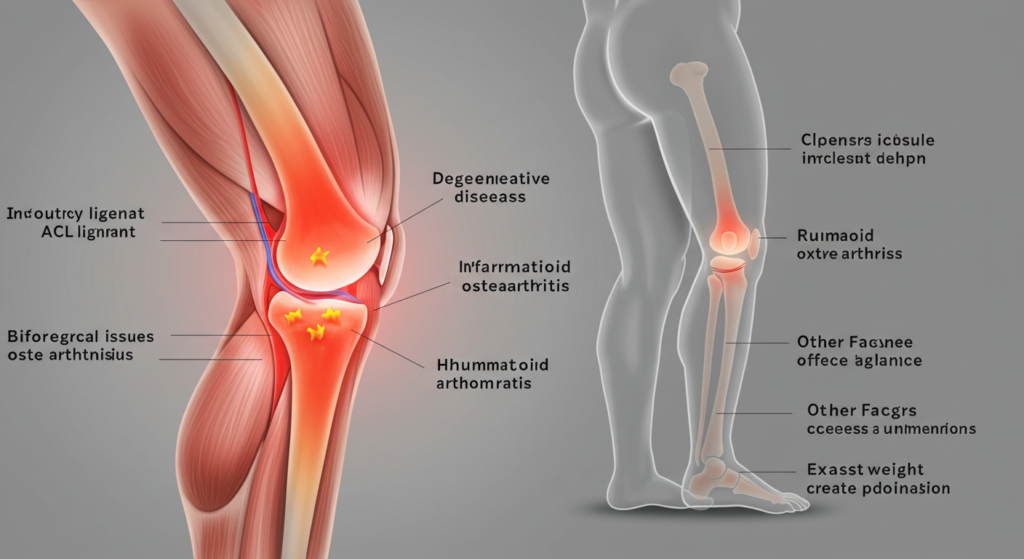

Punca sakit lutut kiri boleh bervariasi dari kecederaan fizikal hingga penyakit degeneratif. Kecederaan seperti ligamen koyak atau kecederaan meniskus adalah antara penyebab utama kesakitan lutut. Sebagai contoh, seorang atlet yang terjatuh semasa berlari mungkin mengalami kecederaan pada lutut kirinya, yang menyebabkan kesakitan yang ketara. Selain itu, penyakit seperti osteoartritis dan rheumatoid arthritis juga boleh menjadi punca sakit lutut kiri, terutamanya bagi mereka yang berusia lebih dari 40 tahun. Oleh itu, memahami punca-punca ini adalah langkah pertama yang penting dalam mencari rawatan yang berkesan.

Kecederaan adalah salah satu punca sakit lutut kiri yang paling umum. Ini termasuk pelbagai jenis kecederaan yang boleh berlaku semasa aktiviti fizikal atau sukan. Salah satu jenis kecederaan yang sering berlaku adalah kecederaan ligamen, seperti ligamen anterior cruciate (ACL) (Sumber: https://orthoinfo.aaos.org/en/diseases–conditions/anterior-cruciate-ligament-acl-injuries/). Kecederaan ini boleh menyebabkan kesakitan yang teruk dan ketidakstabilan pada lutut. Sebagai contoh, seorang wanita yang terjatuh semasa bermain bola sepak mungkin mengalami kecederaan ACL, yang memerlukan rawatan dan pemulihan yang teliti. Dengan memahami punca sakit lutut kiri yang berkaitan dengan kecederaan, individu dapat mengambil langkah-langkah pencegahan yang sesuai untuk mengurangkan risiko kecederaan di masa depan.

Selain itu, kecederaan pada meniskus, yang merupakan tulang rawan di lutut, juga boleh menyebabkan kesakitan dan bengkak. Meniskus berfungsi sebagai penyerap kejutan dan membantu menstabilkan sendi lutut. Apabila meniskus mengalami kecederaan, seperti koyak, ia boleh menyebabkan rasa sakit yang ketara dan kesukaran untuk bergerak. Contohnya, seorang wanita yang mengalami kecederaan meniskus mungkin mendapati bahawa lutut kirinya terasa sakit apabila dia cuba membengkokkan atau meluruskan kakinya. Dengan memahami punca sakit lutut kiri yang berkaitan dengan kecederaan, individu dapat lebih bersedia untuk mendapatkan rawatan yang tepat dan menjalani pemulihan yang berkesan.

2. Penyakit Degeneratif

Penyakit degeneratif seperti osteoartritis adalah punca biasa sakit lutut kiri, terutama pada orang yang lebih tua. Dalam keadaan ini, tulang rawan yang melindungi sendi lutut akan haus dan menyebabkan kesakitan serta kekakuan. Sebagai contoh, seorang wanita berusia 60 tahun mungkin mengalami kesakitan lutut kiri yang semakin teruk selepas melakukan aktiviti harian seperti berjalan atau menaiki tangga. Dengan memahami punca sakit lutut kiri yang berkaitan dengan penyakit degeneratif, individu dapat mengenali tanda-tanda awal dan mendapatkan rawatan yang diperlukan untuk menguruskan keadaan ini.

3. Penyakit Radang

Penyakit radang seperti rheumatoid arthritis adalah punca sakit lutut kiri yang lain yang perlu diperhatikan. Penyakit ini adalah keadaan autoimun di mana sistem imun tubuh menyerang tisu sendi, menyebabkan keradangan yang teruk. Sebagai contoh, seorang wanita yang mengalami rheumatoid arthritis mungkin mendapati bahawa lutut kirinya bengkak dan sakit, terutamanya pada waktu pagi atau selepas berehat. Dengan memahami punca sakit lutut kiri yang berkaitan dengan penyakit radang, individu dapat mengenali simptom awal dan mendapatkan rawatan yang diperlukan untuk menguruskan keadaan ini.

4. Masalah Biomekanik

Masalah biomekanik seperti kaki rata atau ketidakseimbangan otot juga boleh menjadi punca sakit lutut kiri. Kaki rata, di mana lengkungan kaki tidak terbentuk dengan baik, boleh menyebabkan tekanan tambahan pada sendi lutut. Sebagai contoh, seorang wanita yang mempunyai kaki rata mungkin mendapati bahawa lutut kirinya terasa sakit selepas berjalan dalam jangka masa yang panjang. Dengan memahami punca sakit lutut kiri yang berkaitan dengan masalah biomekanik, individu dapat mengambil langkah-langkah untuk memperbaiki postur dan teknik berjalan mereka.

5. Faktor Lain

Punca sakit lutut kiri juga boleh dipengaruhi oleh faktor lain seperti obesiti dan aktiviti berlebihan. Berat badan berlebihan memberikan tekanan tambahan pada sendi lutut, yang boleh menyebabkan kesakitan. Sebagai contoh, seorang wanita yang mempunyai indeks jisim badan (BMI) yang tinggi mungkin mendapati bahawa lutut kirinya terasa sakit selepas berdiri dalam jangka masa yang panjang. Dengan memahami punca sakit lutut kiri yang berkaitan dengan obesiti, individu dapat mengambil langkah-langkah untuk menguruskan berat badan mereka melalui diet yang seimbang dan senaman secara teratur.